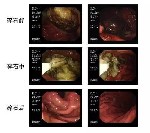

一名中年男性手捂上腹部,痛苦滿面的走進內(nèi)鏡中心預約胃鏡檢查??紤]患者病情,醫(yī)護人員簡單詢問無檢查禁忌后,決定開通綠色通道立即給予行胃鏡檢查。胃鏡進入胃腔后,見較多褐色液體,胃體大彎見一大小約6.0×8.0cm巨大結石,表面附著褐色血液,由于胃結石摩擦,胃竇、胃體、胃角形成多處潰瘍,部分潰瘍表面還在滲血。仔細詢問患者后得知,患者有喜歡進食柿子和山楂的癖好,發(fā)病前兩日患者空腹食用了大量的山楂、地瓜等食物。胃內(nèi)結石如不及時取出或碎解,極有可能會導致消化道出血、穿孔、梗阻,結石變硬后胃鏡下無法取出甚至需外科手術取石等。

因患者反應較大且結石巨大,遂決定在無痛胃鏡下將結石碎解、取出。在麻醉狀態(tài)下,李明峰主任嫻熟的利用內(nèi)鏡下碎石器、圈套器等微創(chuàng)器械成功將結石碎解并大部取出。術后通過禁食、抑酸、增強胃腸動力等處理,患者腹痛癥狀明顯緩解。一周后復查胃鏡,胃內(nèi)結石完全消失,因結石磨損造成的潰瘍基本愈合。